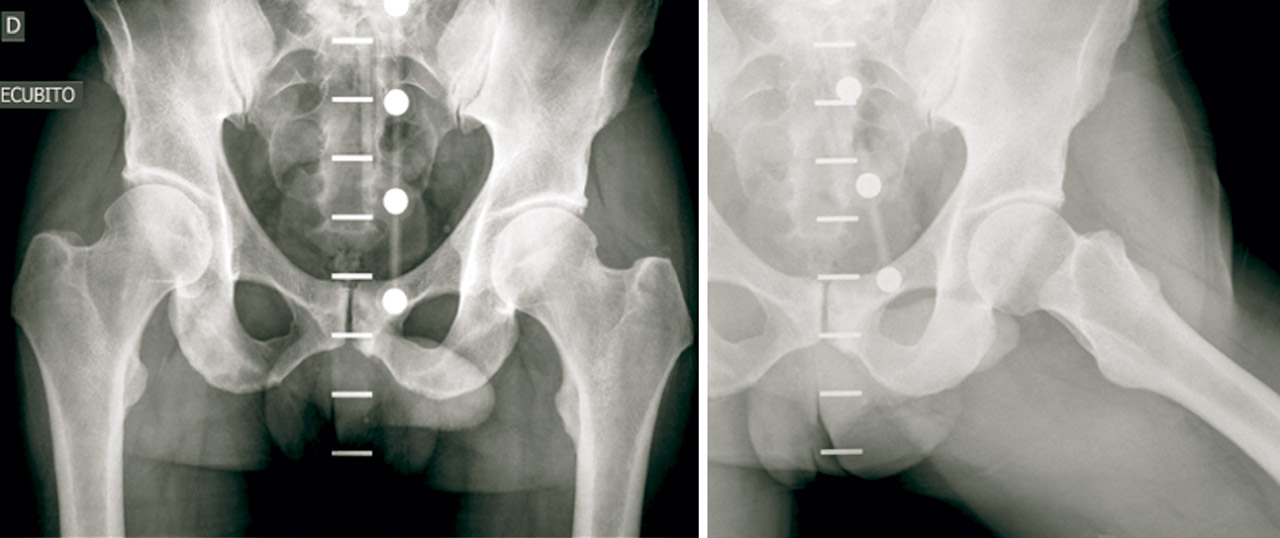

Presentamos el caso de un varón de 48 años, instructor de tenis profesional, sin antecedentes clínicos relevantes. Consulta por coxalgia izquierda incapacitante durante la actividad laboral de unos 18 meses de duración. El examen físico mostró dolor en flexión y rotación interna de la cadera izquierda y una prueba de choque positiva. Se realizaron radiografías para evaluar la presencia de morfologías que pudieran predisponer a un pinzamiento femoroacetabular (Figura 1). No se observó morfología anormal o signos de osteoartritis. El tratamiento inicial incluyó la prescripción de antiinflamatorios no esteroideos (AINE) y la modificación de la actividad física. Se realizó una resonancia magnética (RM) para completar el estudio. Los resultados de la RM no identificaron alteraciones morfológicas o cambios de señal en la cabeza femoral que pudieran sugerir necrosis ósea, focos de osteocondritis, fracturas por estrés, edema óseo u osteoporosis transitoria. Se identificó una lesión del labrum anterior con un quiste paralabral asociado a esta, de 32 × 17 mm (Figura 2). Después de 3 meses de tratamiento conservador sin mejoría clínica, se propuso la escisión quirúrgica y la reparación del labrum. La extirpación quirúrgica se realizó a través de artroscopia mediante técnica fuera-dentro. Todas las estructuras óseas en el compartimento central no mostraron signos patológicos. Se observó una lesión del labrum en su zona anterosuperior (zona 2)(2). En el compartimento periférico, se identificó una gran lesión quística que rodeaba el borde anterosuperior del labrum y el acetábulo (Figura 3). La extirpación completa del quiste se realizó artroscópicamente utilizando material específico para la artroscopia de cadera. No se registraron complicaciones intraoperatorias. La reparación labral se realizó con un sistema de anclaje All-Suture® de tipo Y-Knot® (Conmed). Se inició el protocolo de fisioterapia postoperatoria habitual de nuestro centro, permitiendo la carga parcial con dos muletas al momento del alta con progresión gradual a peso completo en un periodo de 2-3 semanas, seguido de un protocolo de rehabilitación para conseguir el rango completo de movilidad articular y lograr la fuerza completa de la extremidad. En un periodo de 3 meses, el paciente regresó por completo a la actividad física. No se observaron complicaciones.

Figura 1. Radiografía anteroposterior y lateral preoperatoria de la cadera izquierda.